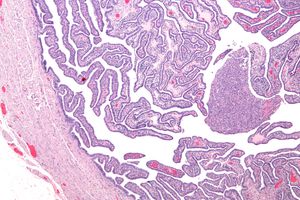

확정적 기준에는 조직병리학적 자궁내막염 증거, 두꺼워진 나팔관, 복강경 검사 소견이 포함된다. 그람 염색/도말은 드물고 비정형적이며 더 심각한 유기체의 식별에 결정적인 역할을 한다.[24] 이전 PID의 복강경 증거가 있는 환자의 2/3는 PID가 있다는 것을 알지 못했지만, 무증상 PID조차 심각한 해를 입힐 수 있다.

복강경 식별은 난관 질환 진단에 도움이 되며, PID 의심 환자에서 65~90%의 양성 예측 가치를 보인다.[25]